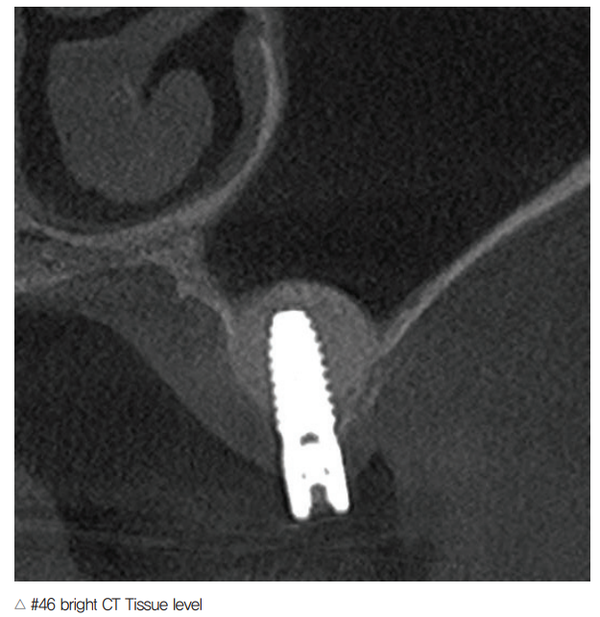

뿐만 아니라 파노라마 촬영 시 Auto Focusd Panoramic 알고리즘을 적용, 선명한 전치부 영상뿐만 아니라 진단에 최적화된 이미지를 제공하기 때문에 환자와의 상담 시 설명하기에 매우 편리하다. 또한 인공 음영 Zero, 임플란트 나사선까지도 세밀하게 확인이 가능하다.

최근 서지컬 가이드의 사용이 증가하면서 CT 영상의 결과물이 CT 구매시 중요한 요 소로 손꼽힌다. Bright CT는 MAR(Metal Artifact Reduction) 기술을 적용해서 메탈 번짐을 최소화 할 수 있고 CT 데이터와 스캔 데이터(STL) 병합 시 편리성이 증가됐다. 메탈의 번짐을 최소화해 인접치의 간섭을 줄일 수 있다는 장점도 있다.

bright CT를 사용하고 있는 정신형(서울 하이안치과) 원장은 “bright CT는 파노라마 촬영 시 blurring을 최소화해 하악 전치부 진단에 편리할 뿐만 아니라 Fixture Thread가 정확히 표현될 정도로 선명한 영상을 구현하기 때문에 최고의 가성비를 가진 제품”이라고 극찬했다.